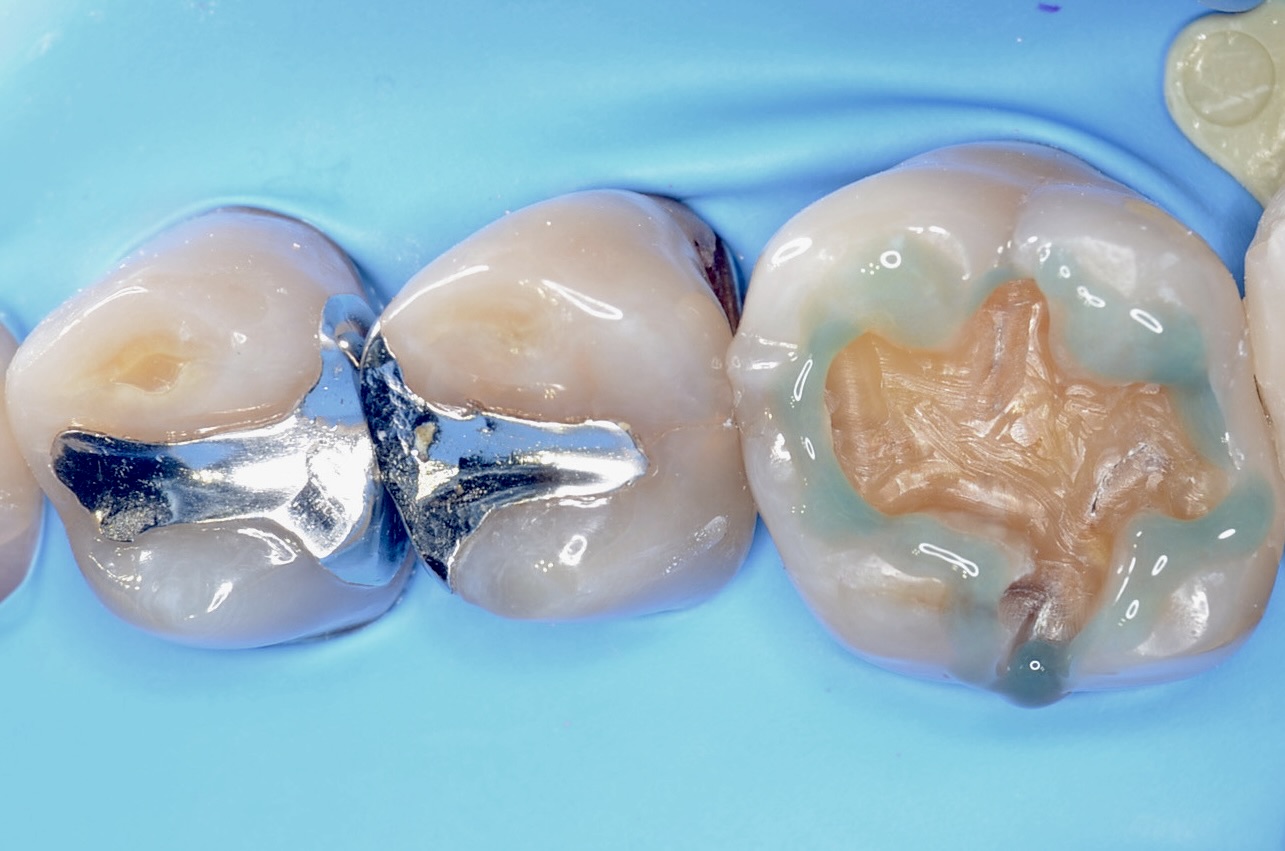

6番のインレーを除去

エナメル質のみを選択的に酸処理をして、接着力を増強させます。 -

5番遠心

虫歯が広がっていました。 -

6番近心

6番の近親も虫歯でした。 -

6番近心ダイレクトボンディング

フロワブルレジンの表面張力を活かし滑らかに充填します。 -